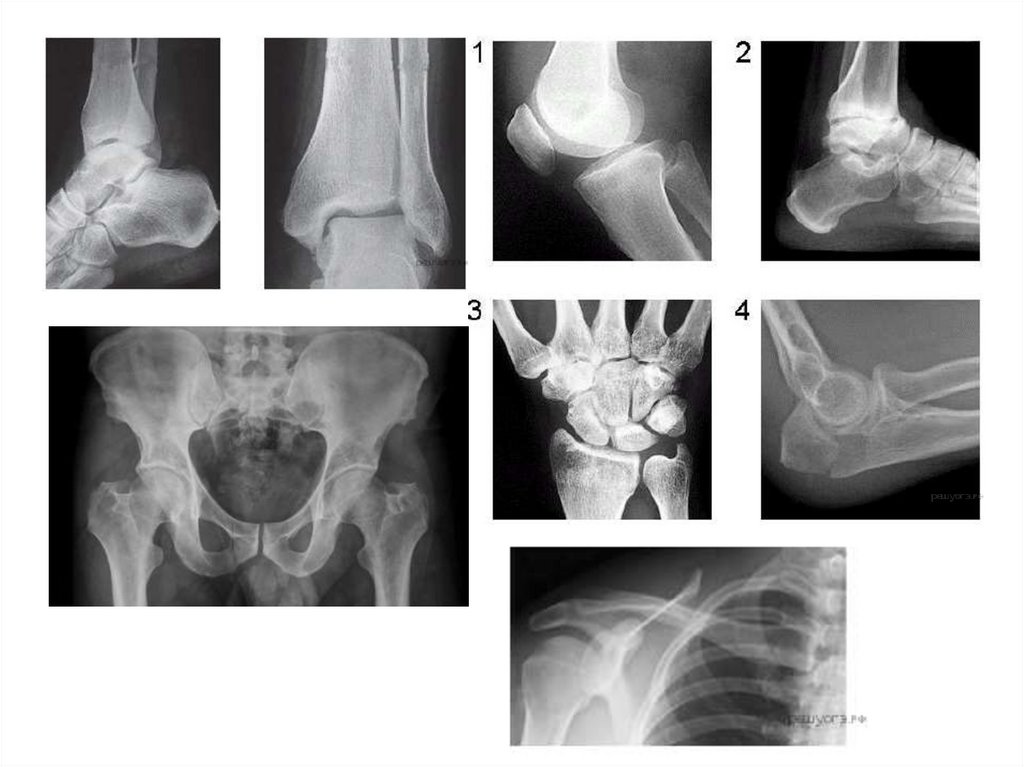

Скелет конечностей

III. СКЕЛЕТ КОНЕЧНОСТЕЙ

ВЕРХНИЕ КОНЕЧНОСТИ

А. ПОЯС ВЕРХНИХ КОНЕЧНОСТЕЙ

1. Лопатки (2)

2. Ключицы (2)

Б. СВОБОДНАЯ КОНЕЧНОСТЬ

1. Плечевая кость

(кость плеча)

2. Локтевая кость (кости

3. Лучевая кость

предплечья)

4. Кости кисти

а) кости запястья

б) кости пясти

в) фаланги пальцев

НИЖНИЕ КОНЕЧНОСТИ

А. ПОЯС НИЖНИХ КОНЕЧНОСТЕЙ

(ТАЗОВЫЙ)

1. Подвздошные кости (2 сросшиеся)

6 2. Седалищные (2 сросшиеся)

3. Лобковые (2 сросшиеся)

1. Бедренная кость (кость бедра)

2. Большая берцовая (кости

голени)

3. Малая берцовая

4. Коленная чашечка

5. Кости плюсны

а) кости предплюсны

б) кости плюсны

4.

Кости таза

1.Подвздошные

2. Лобковые

3. Седалищные